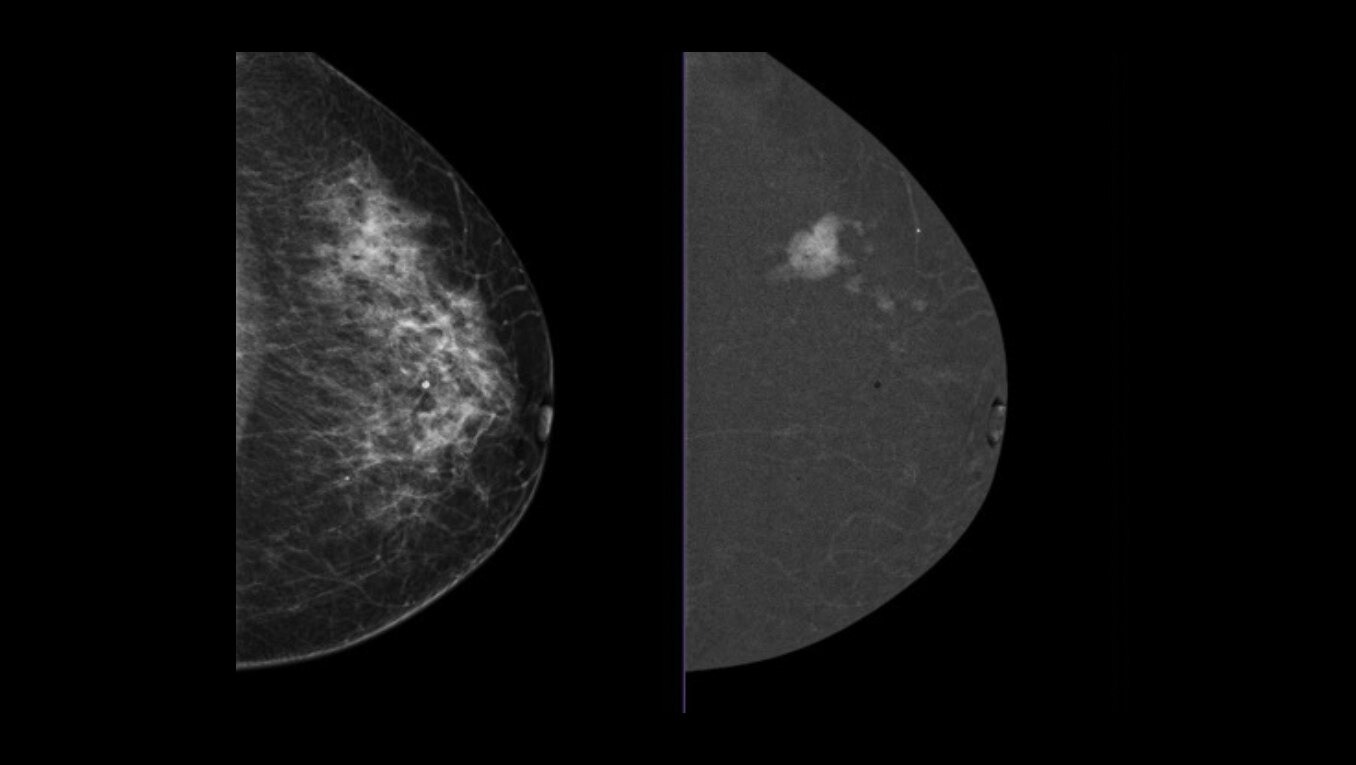

GE HealthCare pioneered this technology in 2010 and is associated with over 200 publications that demonstrate its clinical performance. GE HealthCare’s CEM combines the morphologic and density information similar to a conventional mammogram and the functional vascular information of a breast MRI1. It presents an opportunity to create and implement a more streamlined workflow to help diagnosis breast cancer early. In addition to increasing patient access, our CEM offering boasts high levels of sensitivity and specificity, allowing for the detection of lesions that would otherwise go undetected2,3,4. To ensure your practice can fully leverage the combined power of GE HealthCare contrast mammography solutions, we introduce Pristina Bright our comprehensive CEM package with complete support, from training to service, for your successful implementation.